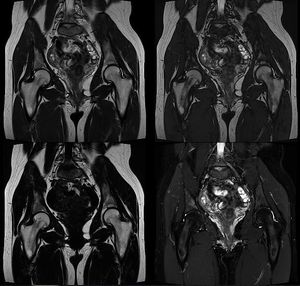

The Dixon technique is based on the chemical shift. With this technique two series of images are acquired. In the first series the signal from fat (Sf) and water (Sw) protons are "in-phase" (Sin). In the second series the signal from fat and water protons are "opposed-phase" (Sop). A separate fat and water image can then be calculated from the equation: Sin = Sw + Sf Sop = Sw – Sf Sin + Sop = [(Sw + Sf) + (Sw - Sf)] /2 = (2 Sw) /2 = Sw Sin - Sop = [(Sw + Sf) - (Sw - Sf)] /2 = (2 Sf) /2 = Sf Dixon delivers up to 4 contrasts in one sequence: in-phase, opposed-phase, water and fat images (figure). Fig. T2-W TSE Dixon images. Dixon technique has the ability to deliver up to 4 contrasts in one measurement. In-phase (upper left), opposed-phase (upper right), fat (bottom left) and water (bottom right) images of the pelvis. Image dataset acquired at 3.0 Tesla. Images courtesy of Bac Nguyen.